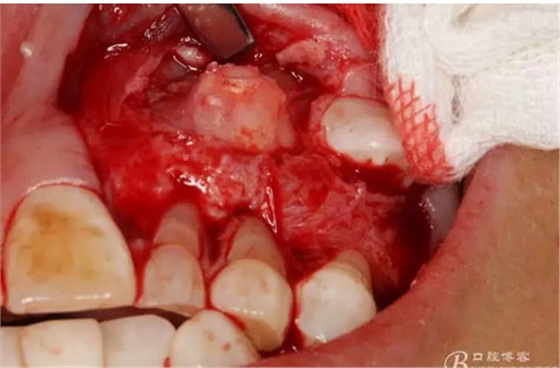

圖19.生理鹽水沖洗骨腔,修整骨腔表面

圖21.術中拍全景片,看是否有牙瘤殘留,發(fā)現(xiàn)左側(cè)乳Ⅱ根尖區(qū)還有少量致密鈣化物,建議拔除左側(cè)乳Ⅱ、,患者要求保留兩個乳牙。經(jīng)協(xié)商,遺留極少量鈣化物,不影響整體愈合。通過骨腔探查,發(fā)現(xiàn)左側(cè)乳Ⅱ、Ⅲ根尖區(qū)未破壞,骨壁尚完整。同意遺留部分鈣化物。有點缺憾,為了保留乳牙和患者的美觀及功能。定期觀察遺留部分的發(fā)展變化

圖22.為了保留兩顆乳牙,不再去除遺留部分鈣化物,遂膠原蛋白海綿填塞兩個缺損骨腔。